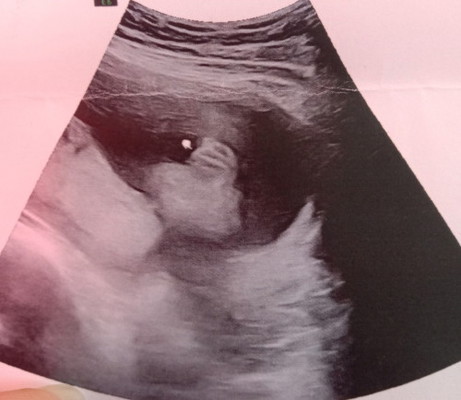

แม่ๆช่วยดูหน่อยค่ะ

ผญ.จริงๆใช่ไหมค่ะ ☺️☺️หมอบอกว่าผญ.แต่ก็อยากฟังความเห็นจากแม่ๆด้วย

นี่ก็ผู้หญิงค่ะแม่ ยินดีด้วยนะคะ🥰

ผู้หญิงค่ะ กลีบน้องชัดเลย😅😍

ผู้หญิงคะเห็นกรีบน้องชัดมากๆคะ

ดูเหมือนเป็นผู้หญิงจ้า คุณแม่

ผญ.ค่าแม่ ยินดีด้วยนะค้า

มาเป็นกลีบเลยค่ะคุณแม่

ผู้ญค่ะคุณแม่🥰